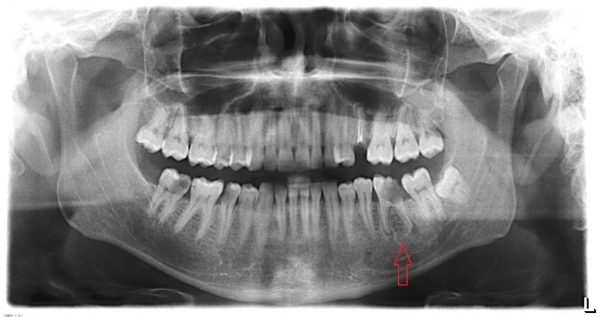

Сделал снимок, его и прикрепляю (больной зуб отметил). Стоматолог снимок не видел еще.

В зубе на верхушках корней имеется обширный воспалительный процесс. Данный зуб скорее необходимо удалить, шансы на спасение теоретические и крайне минимальные. Стоматолог крайне неграмотно, без наличия снимка провёл лечение.